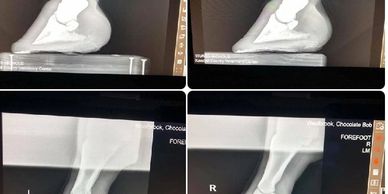

Patient: Andy 10 yr AQHA - Diagnosis: Founder, Laminitis, Ring Bone, white line disease - Treatment: Pain meds, therapeutic shoeing, resected (3 times) over 4 years. Time lapse on photo collage is 2 months. Video was taken 2 weeks Updates will be posted as work progresses.